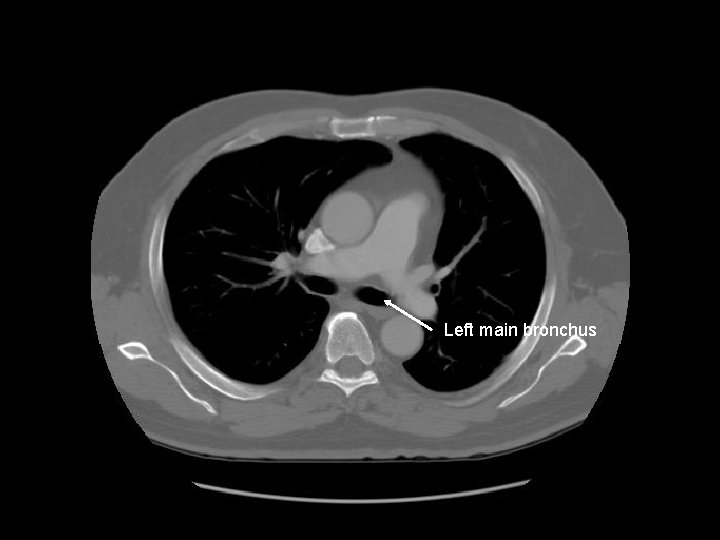

Left main bronchus